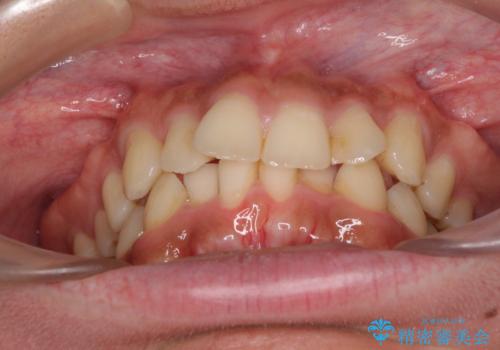

前歯のデコボコをスッキリ改善 インビザライン矯正

- 上下前歯のデコボコを気にして来院された患者様です。

全体的に叢生は軽度であったため、インビザラインにて矯正治療を行うこととしました。

デコボコの改善はもちろん、下顎前歯が隠れてしまうディープバイトも一緒に改善することができ、奥歯への負担を軽減することができました。